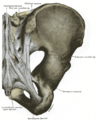

Парные тазовые кости спереди соединяются при помощи лобкового симфиза, а сзади прикрепляются ушковидными поверхностями к одноимённым образованиям крестца, образуя парные крестцово-подвздошные суставы. Каждая из тазовых костей в свою очередь образована тремя составляющими: подвздошной костью, седалищной костью и лобковой костью, тела которых на наружной поверхности образуют вертлужную впадину — суставную ямку для головки бедренной кости, с которой образуют тазобедренный сустав.

- Крестцово-подвздошный сустав (лат. articulatio sacroiliaca) — образован ушковидными поверхностями тазовой кости и крестца. Включает связки: 1) вентральные крестцово-подвздошные (ligg.sacroilica ventralia), 2) дорсальные крестцово-подвздошные (ligg.sacroilica dorsalia) 3) межкостные крестцово-подвздошные (ligg.sacroilica interossea) 4) подвздошно-поясничные (ligg.iliolumbale).

- Лобковый симфиз (лат. symphysis pubica) — соединяет симфизиальные поверхности обеих лобковых костей, между которыми расположен межлобковый диск (discus interpubicus).

- Крестцово-бугорная связка (лат. lig. sacrotuberale) — идёт от седалищного бугра к латеральным краям крестца и копчика.

- Крестцово-остистая связка (лат. lig. sacrospinale) — соединяет седалищную ость с крестцом и копчиком.

- Запирательная мембрана